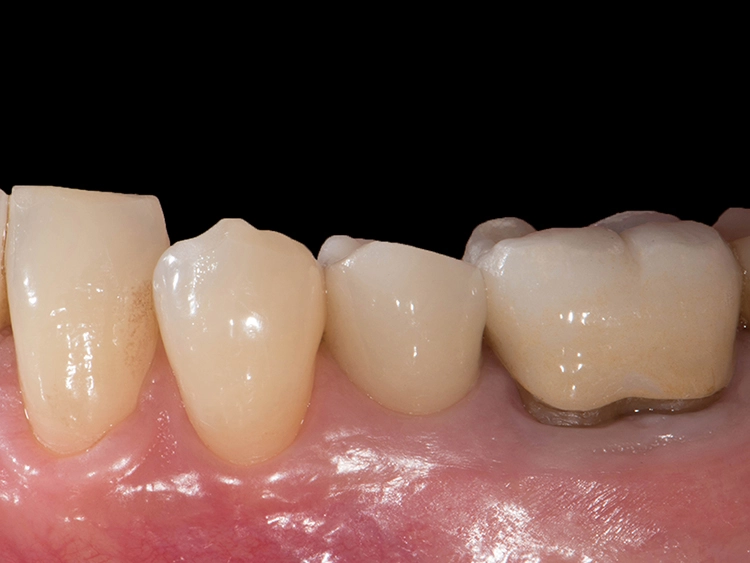

Zweiteilige Implantatsysteme würden darüber hinaus mit einer höheren prothetischen Flexibilität punkten, weil die Aufbauten individueller gestaltet werden können. Dr. Röhling: „Das kann ein Vorteil sein, wenn etwa die prothetische Achse korrigiert werden muss.“ Hinzu kommt, dass bei Anwendung von zweiteiligen Systemen eine Zementierung, die für Fehlerquelle anfällig gesehen wird, entfällt, da sie eine reversibel verschraubte Befestigung erlauben, während bei einteiligen Implantaten die Suprakonstruktion nur zementiert gestaltet werden kann (siehe Fallbeispiel, Abbildungen 1 bis 10).